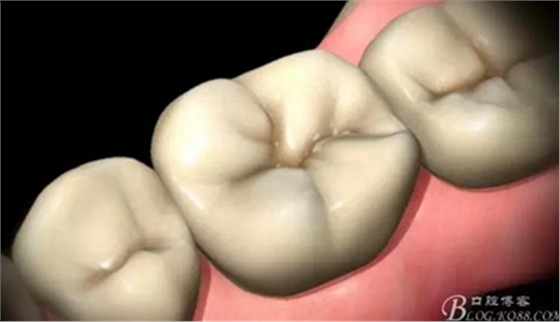

完成

高嵌體病例圖片